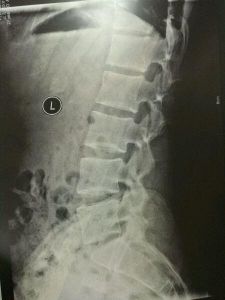

①臨床上出現頸脊強損害的表現。②X線片上顯示椎體後緣骨質增生、椎管狹窄。影象學證實存在脊髓壓迫。③除外肌萎縮性脊膀例索硬化症、脊髓腫瘤、脊髓損傷、繼發性粘連性蛛網膜炎、多發性末梢神經炎。

關於椎動脈型頸椎病的診斷問題是有待於研究的問題。①曾有猝倒發作。並伴有頸性眩暈。②鏇頸試驗陽性。③X線片顯示節段性不穩定或樞椎關節骨質增生。④多伴有交感症狀。⑤除外眼源性、耳源性眩暈。⑥除外椎動脈I段(進入頸6橫突孔以前的椎動脈段)和椎動脈III段(出頸椎進入顱內以前的椎動脈段)受壓所引起的基底動脈供血不全。⑦手術前需行椎動脈造影或數字減影椎動脈造影(DSA)。